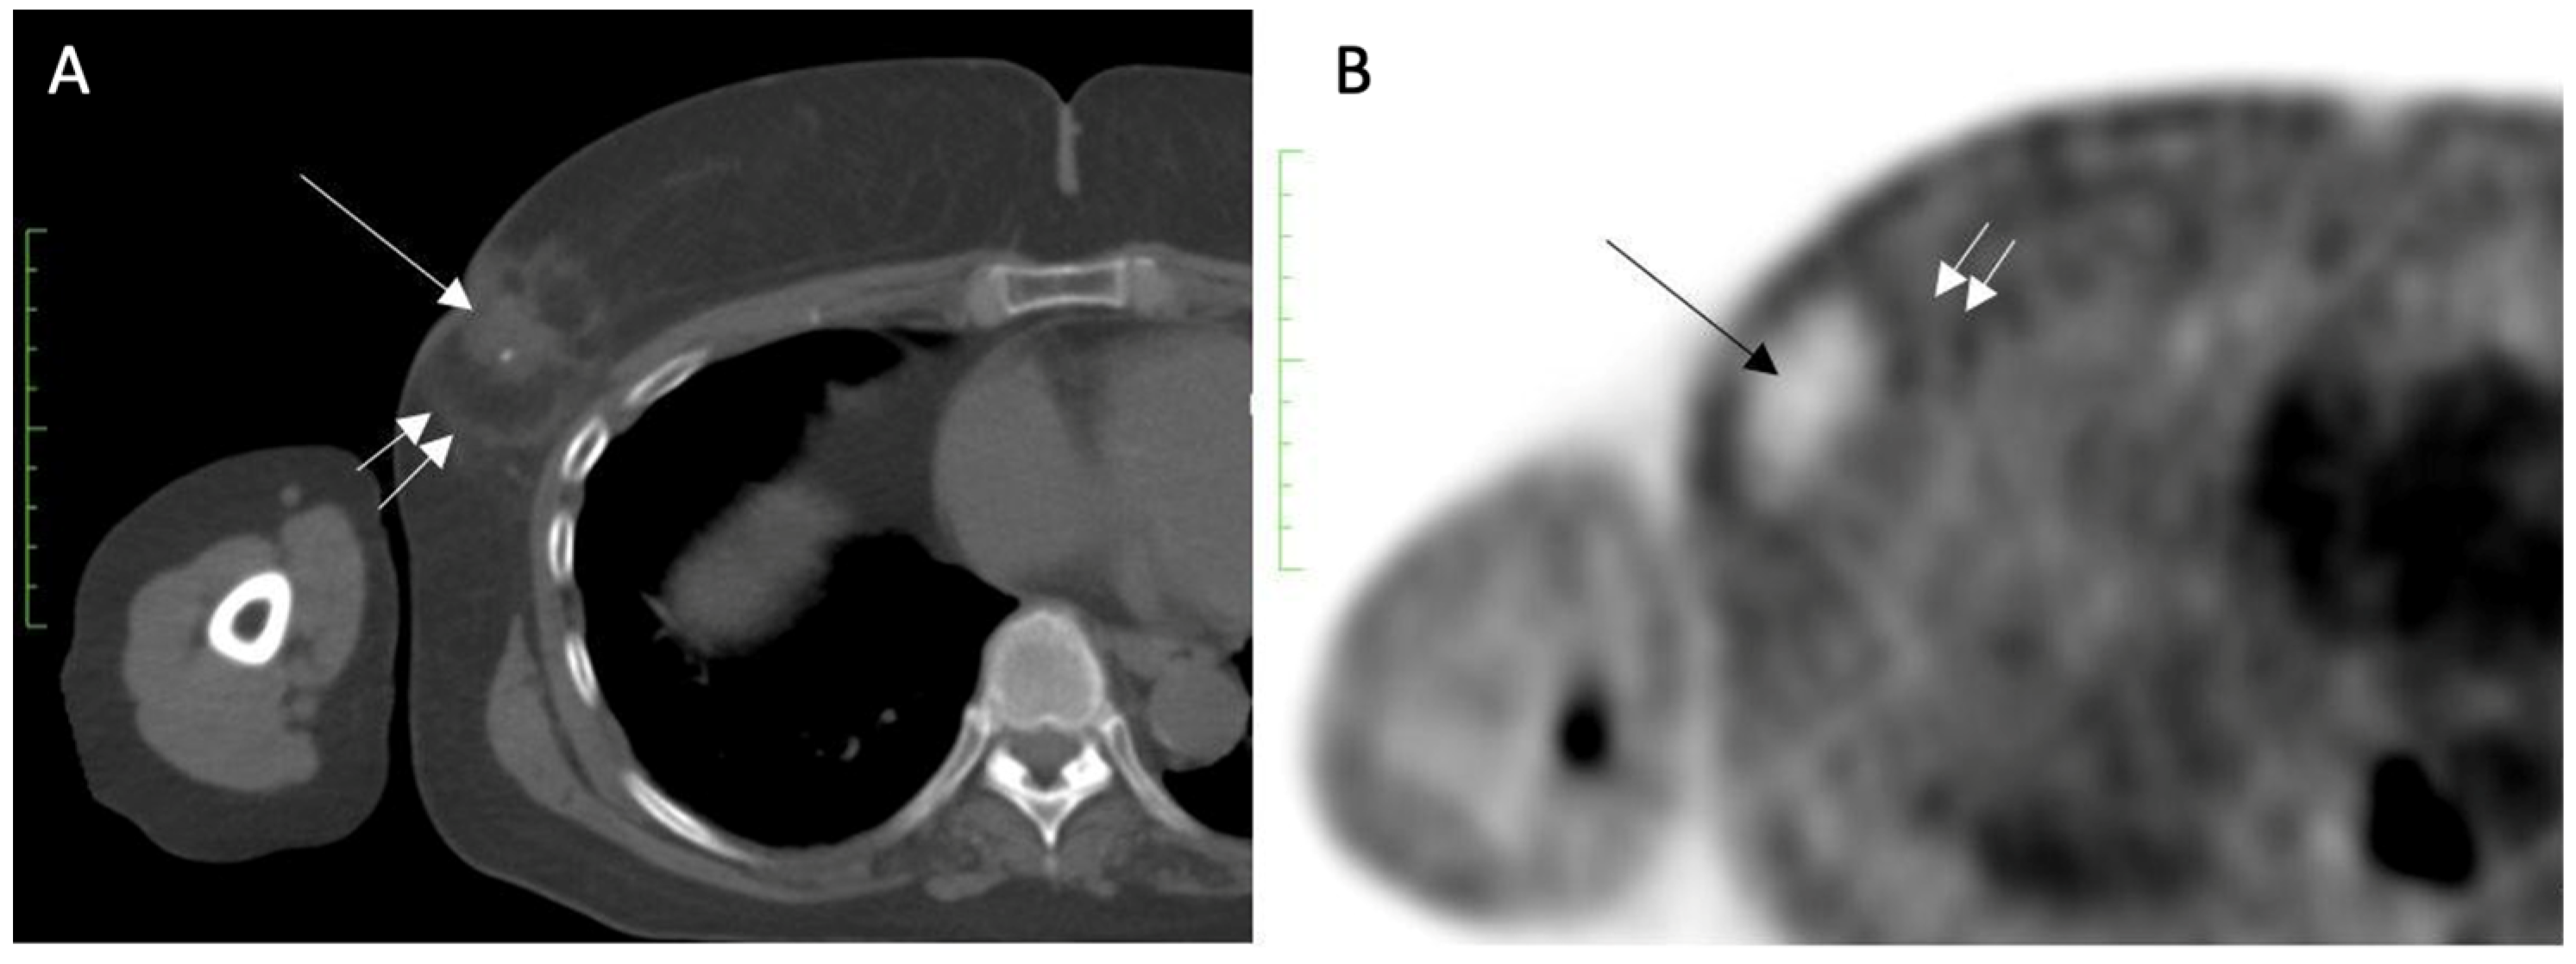

Staging for Distant Metastasis. It is reasonable to assume that the principles guiding cancer staging for cryoablation patients would mirror the staging recommendations outlined in the most recent version of the NCCN guideline. For example, the current version of the NCCN guideline recommends routine whole-body scans only for patients with stage III or IV breast cancer for detection of metastasis in the lung, liver, or other internal organs [9]. Routine staging for stage III and IV breast cancer may consist of computed tomography (CT) scans of the chest and abdomen, with or without pelvic scans or 18F-fluorodeoxyglucose positron emission tomography (FDG-PET/CT) scans. Although many bone metastases may be detected by FDG-PET/CT, dedicated staging for bone metastases may be accomplished with a nuclear medicine bone scan or a sodium fluoride PET/CT scan.

- Target cryoablation of the original tumor volume. Although neoadjuvant systemic therapy might induce the complete radiographic disappearance of the cancer, individual cancer cells or microscopic clusters of cancer cells could persist throughout the span of the original cancer (Figure 19). Therefore, targeting the original tumor volume plus a surrounding ablation margin has a greater potential to achieve complete ablation at the cancer site. This strategy contrasts with how patients are managed surgically after neoadjuvant systemic therapy, where the ability to perform microscopic examination of the surgical margins permits the initial excision of a smaller volume of tissue followed later by margin re-excision if the microscopic assessment reveals residual cancer at the surgical margin.

Figure 19. Mammograms performed before (A) and after (B) chemotherapy showing representative locations (indicated by “X” marks) where bracketing biopsy site markers can be placed before starting chemotherapy to mark the edges of the white, dominant cancer dimensions in the event the mass is no longer visible after chemotherapy. Figure B shows the same breast after completing chemotherapy showing complete resolution of the mass and the representative locations of bracketing site markers (indicated by “X” marks) placed before chemotherapy to outline the original tumor dimensions.